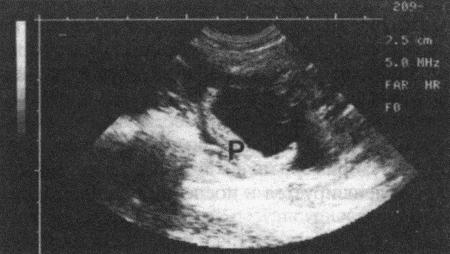

Фиг. 11.6.

Ультразвуковое изображение плодного яйца в продольном сечении, видна С-образная зонарная плацента (Р). Датчик на 5 МГц, шкала в см